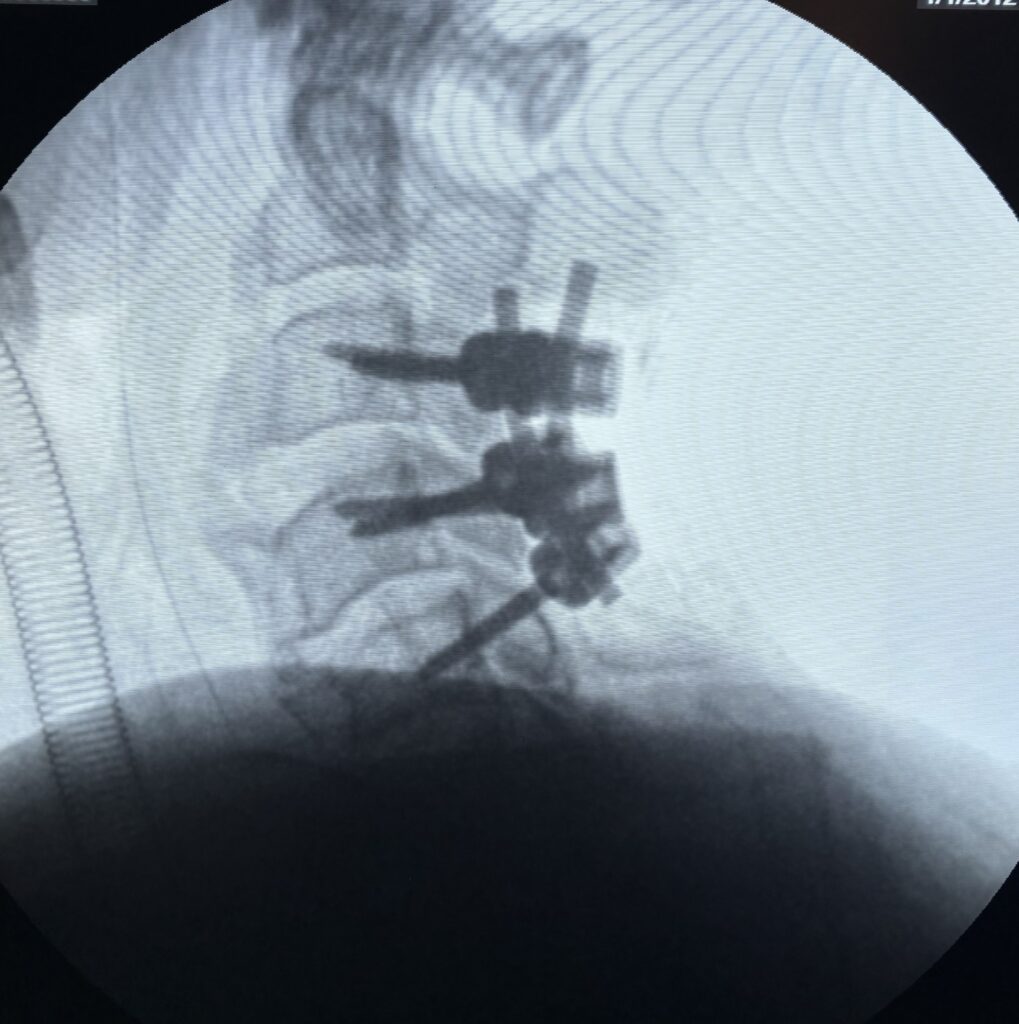

- Discectomy: Removal of damaged disc material.

- Laminectomy: Relieves pressure on spinal nerves.

- Spinal fusion: Stabilizes the spine in advanced cases.

Modern spine surgery is often minimally invasive, which reduces recovery time and hospital stay.

Cases treated by Spine Specialist Dr. Gaurav Sandeep Gupta